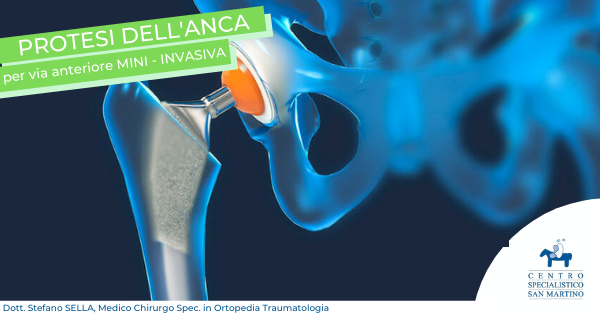

Centro Specialistico San Martino – La Nostra Missione

Il Centro Specialistico San Martino si pone come obbiettivo mettere al centro dell’attenzione l’esigenza dei nostri clienti, del loro stato di salute, nel rispetto della persona stessa e della loro privacy. Avvalendosi di un equipe di professionisti il Centro Specialistico persegue al meglio questa missione, migliorando nella qualità attraverso l’analisi dei risultati e l’applicazione dei principi etici.

Al Centro Specialistico San Martino sito a Vergiate (Varese), raccordo tra i principali ospedali della provincia (Gallarate, Varese, Angera, Cittiglio, Busto Arsizio, Arona), facilmente accessibile dall’autostrada A8 uscita Sesto Calende/Vergiate e a 15Km dall’aeroporto di Milano Malpensa, sono attivi servizi di Medicina Specialistica, Psicoterapia, Disturbi dell’apprendimento e del linguaggio, Recupero Funzionale, Fisioterapia, Ostepatia, Servizi per le Aziende e altro ancora. La struttura è dotata di ampio parcheggio nonchè di parcheggi riservati all’utenza. Sita al piano terra è perfettamente conforme alle normative sulle barriere architettoniche. Internamente la struttura è dotata di comodi corridoi e studi confortevoli. L’attività si svolge in area funzionale all’accoglienza e con personale adeguatamente formato anche all’assistenza di utenza con limitata capacità motoria o sensoriale, oltre che di bambini in età prescolare e scolare.